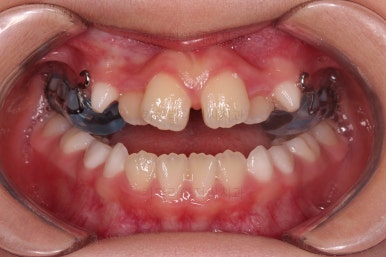

마찬가지로 초진 시 입안의 모습이에요.

아래 앞니가 윗니보다 앞에 있는 "반대교합" 즉, 거꾸로 물려있는 상황이었고요.

어금니 쪽을 보시면(왼쪽 위 사진) 윗니 어금니도 아래 어금니보다 안쪽으로 들어와 있는 "어금니 반대교합"도 있는 상황이었어요.

즉, 윗니가 있는 위턱뼈가 3차원적으로 작은 상황이었던거죠.

이렇게 아랫니들이 윗니보다 앞으로 나와있는 형태의 부정교합을 "앵글씨 3급" 부정교합이라고 합니다.